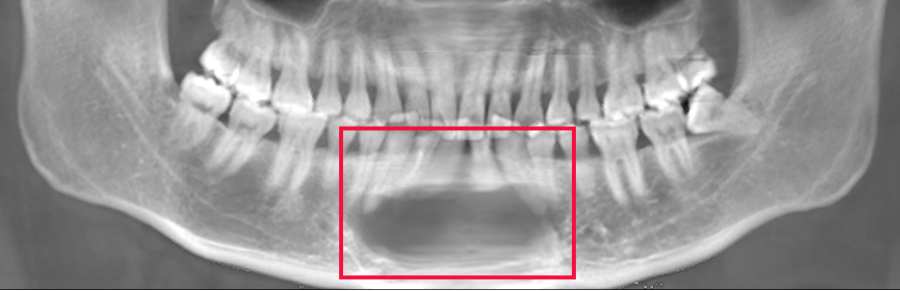

智齿引起下颌骨囊肿(李延超医生提供)

他的这颗智齿不但完全阻生,而且是朝下方“横着长”的,位置藏得很深。智齿周围的牙囊膨胀形变,不断增生分泌物质,下颌骨受压造成骨质吸收,

形成了一个2.5cm*2cm,约有鹌鹑蛋大小的囊性病变(颌骨含牙囊肿)。

正常的下颌骨高度应该有3厘米左右,因骨质吸收,现高度仅剩下不到5毫米。

如果不小心磕碰到下巴,就可能发生下颌骨骨折。